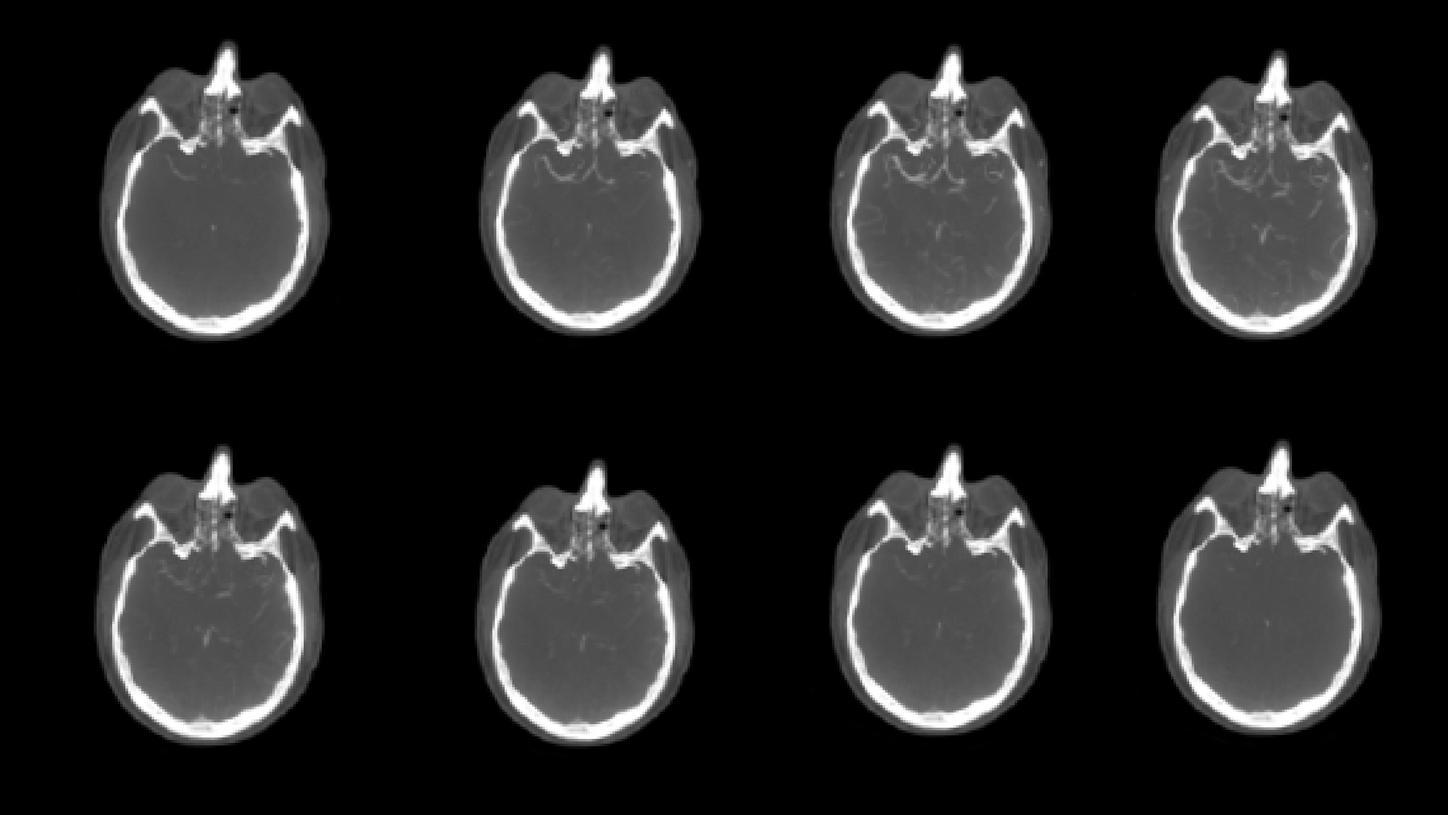

El syngo DynaCT Multiphase consta de 10 rotaciones consecutivas que dan como resultado 10 volúmenes. Comience la inyección con el inicio de la adquisición de la serie. Los primeros dos volúmenes se requieren como serie de máscara para la posible reconstrucción de los mapas de perfusión.* Los otros 8 volúmenes son series de llenado.

*Se requiere software de terceros. El cálculo de mapas de perfusión aún no está disponible comercialmente.

Primera ejecución de syngo DynaCT Multiphase antes de la trombectomía